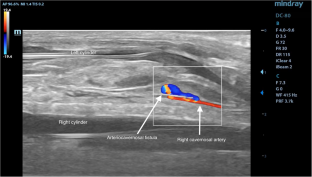

Penile prosthesis implantation is a surgical option for erectile dysfunction when other treatments fail or the patient prefers implantation. Although penile prosthesis is generally considered safe and effective, various complications have been reported in the literature. High-flow priapism, resulting from an arteriovenous fistula between the cavernosal artery and the corpora cavernosa, is a rare complication after penile prosthesis implantation. Managing the condition as autoinflation may lead to unfortunate complications. A 54-year-old male patient underwent a penile prosthesis implantation due to erectile dysfunction lasting for 5 years. Doppler ultrasound revealed arterial insufficiency that was refractory to oral and intracavernosal treatments. A 3-piece inflatable penile prosthesis (Coloplast – Titan) was implanted through a midline penoscrotal incision without any complications. The patient reported uncontrolled tumescence after activating the device, which led us to suspect autoinflation. The final diagnosis was high-flow priapism due to an arteriovenous fistula in the cavernosal artery. The patient was given an antiandrogenic medication and the prosthesis was deflated for 3 months. The fistula closed without any additional intervention. High-flow priapism is a rare but potential complication of penile prosthesis implantation. Careful evaluation and management of patients’ symptoms are necessary for diagnosing and treating this condition. This case highlights the importance of considering high-flow priapism as a potential cause of uncontrolled tumescence after penile prosthesis implantation and the possibility of successful non-surgical management.